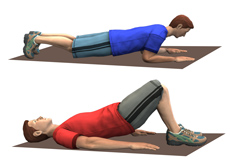

Back Pain Exercises

Strenuous activities of daily living can stress the back resulting in pain. It is natural at this time to withdraw from activity and rest, but is not helpful in the long run and may actually slow down the healing process.

Physical therapy for the Spine

Physical therapy is one of the foremost necessary treatment modes of recovery for back pain. A referral to physiotherapy sometimes is created by your spine surgeon. A physical therapist is a well-trained, skilled health care professional who facilitates improving movement and manages the pain by safe stretching, conditioning, and strengthening exercise techniques.